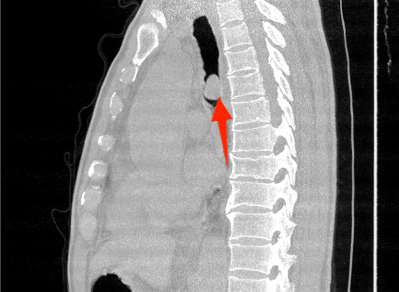

近年来,贵州航天医院各科室紧跟医学前沿,不断强技术、补短板,大力开展新技术、新项目,完成了许多高精尖、高难度、本地区“首例”的技术,填补了医院医疗技术空白,满足了群众日益增长的医疗需求。 贵州航天医院呼吸与危重症医学科是贵州省内呼吸疾病治疗规模最大,诊疗项目最全的呼吸疾病品牌科室,呼吸介入技术达到了全国先进水平,在贵州省内处于领先的地位。 本期,我们将为大家带来呼吸与危重症医学科特色技术——气道支架置入技术治疗呼吸不畅(已纳入乙类医保报销)。 案例分享 一患者因出现呼吸困难、气急等症状,听说我院呼吸与危重症医学科呼吸系统疾病诊疗实力在省内属于前列,慕名前来就诊,入院后,呼吸与危重症医学科为患者完善了胸部CT检查,提示:左主支气管肿瘤生长至气管下段,左肺不张,对此,科室立即组织多学科(MDT)讨论,对患者进行全面的诊断评估,诊断为:左肺鳞癌,左肺不张,气管下段内生型狭窄,左主支气管堵塞。 在充分了解患者及家属的治疗需求和征得治疗同意后,为进一步减轻患者呼吸困难症状,决定为患者实施气道支架置入技术,通过将支气管镜插入到气管中,使用气道球囊扩张器对狭窄的气道进行扩张,在病变部位置入支架扩张狭窄的支气管后,患者安全返回病房。 国产镍钛记忆合金支架植入步骤 术后,患者左主支气管通畅。 什么是气道支架置入技术 气道支架置入技术是一种用于治疗气道狭窄及气道相关性瘘等疾病重要的手段,尤其适用于因恶性肿瘤或其他原因导致的呼吸困难患者。是利用一种保持管腔完整性的人造装置——支架并应用支架置入器在X线透视或支气管镜直视下将支架置入气道保持气道通气功能的一种方法。 目前气道支架最常见的类型有可膨胀金属气道支架、硅酮支架及混合性支架等,以可膨胀金属支架为最常用。 气道支架置入技术原理 是将具有一定张力和弹力的支撑物(即气管支架)置入气道内,将狭窄或塌陷的气道撑开,从而维持气道通畅,或堵住破裂的瘘口。根据气管、支气管不同部位的解剖特点和病变情况,选择对应型号的支架,并通过气管镜的指引,在病灶位置植入合适的支架,也可根据气道的收缩性、不规则性和狭窄程度,进行适当调整。 气道支架置入技术优势 (一)快速缓解呼吸困难:支架置入能够迅速撑开狭窄或塌陷的气道,显著改善患者的呼吸困难症状。 (二)降低气道塌陷风险:对于某些肿瘤或炎症引起的气道狭窄,支架置入可以稳定气道结构,降低气道塌陷和窒息的风险。 (三)创伤小、恢复快:相较于传统手术,气道支架置入术具有微创的特点,患者术后恢复较快,痛苦较小。 气道支架可减轻或抵抗外部压力,扩大狭窄气道后,中央气道梗阻的症状和体征可立即减轻或消除,肺功能、运动能力及生活质量也得到改善。理想的气道支架应具备对气道壁物理性刺激小、置入后不移位、能阻止肿瘤或组织向支架内生长、不影响排痰、可以并容易回收等特点。 贵州航天医院 呼吸与危重症医学科专家团队 廖江荣 国务院政府特殊津贴专家 二级教授 主任医师 贵州航天医院副院长 国家级学术任职: 第二届中国医药教育协会介入微创专业委员会呼吸分会副主任委员 中国抗癌协会肿瘤微创治疗专业委员会常务委员 中国防痨协会结核病转化医学专业分会常务委员 第一届中国人体健康科技促进会呼吸介入专委会常务委员 中国医疗保健国际交流促进会结核病学分会第三届委员会常务委员 中国抗癌协会肿瘤微创治疗专业委员会粒子治疗学组第四届委员会委员 中华医学会结核临床专业委员会内镜介入委员 中华医学会放射学分会第十五届委员会介入学组呼吸系统介入专业委员会委员 北京健康促进会中青年专家委员会胸部疾病精准活检分委会副主任委员 中国医师协会介入医师分会第二届委员会肿瘤消融专业委员会委员 中国结核病防治综合质量控制专家指导委员会委员 亚洲冷冻治疗学会常务委员 世界内镜医师协会呼吸内镜协会常务理事 内镜临床诊疗质量评价专家委员会委员 “西部呼吸介入联盟”副理事长 专业擅长: 呼吸系统(肺)疑难病的诊断及危重病的抢救,呼吸系统(肺)感染性、疑难性疾病介入快速诊断(ROSE),尤其在肺癌、肺小结节早期诊断,肺癌微创综合靶向治疗,难治性、复治性、重症肺结核诊疗,硬质支气管下复杂性气道狭窄诊治,纤支镜介入治疗气道肿瘤、结核、气道狭窄(球囊扩张、支架植入、高频电刀、氩气刀、冷冻、灌洗、注药、微波消融),间质性肺疾病的诊疗上具有极高水平;带领团队勇于创新,在贵州省率先开展多项新技术、新疗法,如CT引导下及纤支镜下I125粒子植入及CT引导下微波、射频消融介入治疗肺癌等多项新技术,带动了贵州省肺部疾病的介入治疗水平提高。 蒋 婷 呼吸与危重症医学科 总负责人 副主任医师 专业擅长:从医20余年,在呼吸系统疾病、介入呼吸病学、肺部结核、肺部肿瘤等方面具有丰富的临床经验和专业技能,尤其是慢性阻塞性肺疾病、支气管扩张、肺结核、耐药肺结核、肺癌、胸腔积液等肺部疾病的诊治、微创介入、危重病患者抢救。 现任中国防痨协会人兽共患结核病专业分会委员,中国女医师协会第一届介入专业委员会委员,贵州省基层呼吸疾病防治联盟-间质性肺疾病联盟委员,贵州省防痨协会第七届理事会理事,贵州省中西医结合学会呼吸专业委员介入呼吸病学组委员,贵州省遵义市中医药学会中西医结合肺病(呼吸)分会副主任委员,贵州省遵义市中医药学会中医肿瘤专业委员会常委;发表论文数篇,参与并主持多项科研项目。 李桂凤 呼吸与危重症医学科 三病区 主任 副主任医师 专业擅长:从事呼吸系统疾病、结核病学、介入呼吸病学、肿瘤综合治疗、呼吸康复等临床工作20余年,擅长呼吸内科常见病、多发病及疑难重症危重病症的诊治,尤其对重症疑难结核及耐药结核病、介入治疗(肺)呼吸系统疾病、呼吸危重病抢救等方面具有较高诊疗水平。 中国防痨协会非结核病专业委员会委员,贵州省中西医结合学会第六届呼吸专业委员会委员,贵州省康复学会睡眠障碍康复专业委员会委员,遵义市呼吸内科医疗质量控制中心委员,遵义市落实民生实事结核病筛查阅片专家组成员;主持及参与实用新型专利3项。 周裕祥 呼吸与危重症医学科 四病区 主任 副主任医师 专业擅长:经皮肺介入、经血管介入诊疗技术。 贵州省中西医结合学会呼吸专业委员会介入呼吸病学组常务委员,中国医师协会呼吸医师分会介入呼吸病学工作委员会呼吸病血管介入学组委员,贵州省中西医结合学会呼吸学分会委员,遵义市医学会放射肿瘤治疗学分会委员,中国医药教育协会介入微创呼吸分会委员,北京健康促进会中青年专家委员会胸部疾病精准活检分委会委员;曾赴重庆医科大学RICU、珠海市人民医院介入科进修学习。 杨 芳 呼吸与危重症医学科 内镜中心 主任 副主任医师 专业擅长:从事临床工作约16年,对呼吸危重病的救治有独到的见解,尤其擅长呼吸系统疾病的介入诊疗,对呼吸内镜下的诊治及经皮肺穿刺诊疗技术具有丰富的临床经验。 亚洲冷冻治疗学会委员,中国医药教育协会介入微创呼吸分会委员,西南结核病医院联盟第二届委员会秘书/委员,贵州省中西医结合学会第六届呼吸科专业委员会委员,贵州省中西医结合学会呼吸专业委员会介入呼吸病学组秘书,贵州省中西医结合学会呼吸专业委员会基层康复学组副组长,贵州水利电力医学科学技术会高原医学分会委员,遵义市中医院学会中西医结合肺病(呼吸)分会秘书/常务委员,遵义市医学会肿瘤学分会(第二届)委员,遵义市医学会放射肿瘤治疗学分会第二届委员;主持及参与科研课题多项,参编著作《呼吸内镜操作技术规范》、《介入结核病学》,发表论文数篇。 贵州航天医院 呼吸与危重症医学科专家团队 贵州航天医院呼吸与危重症医学科以呼吸危重症和介入呼吸病学为强力推手,以肺部感染性疾病及肺癌、肺小结节的早期精准诊疗、慢性呼吸疾病康复治疗为特色,以人才团队建设为核心的科室发展模式,现已成为省内呼吸疾病治疗规模最大,诊疗项目最全的呼吸疾病品牌科室。是贵州省医学重点学科、临床医学重点专科建设单位,遵义市首批呼吸重点学科、重点专科建设单位。是国家卫健委能力建设和继续教育肿瘤微创介入建设中心、贵州省县级医院微创介入培训中心、遵义市呼吸疾病临床医学中心。是国家呼吸医疗质量控制与管理哨点医院、遵义市呼吸内科专业医疗质量控制中心。是中国医药教育协会介入微创呼吸分会呼吸介入技术培训中心单位;国家卫健委海医会呼吸分会ROSE专委会“诊断性介入肺脏病学快速现场评价”培训基地;中国肺癌防治联盟“贵州航天医院肺结节诊治”分中心,中国人体健康科技促进会呼吸介入技术培训基地,贵州省中西医结合会呼吸学分会呼吸介入专委会主委单位。 基本情况 平均每年开展气管镜诊疗约4000例,经皮肺穿刺介入诊疗近千例,开展的项目包括经支气管镜(软、硬)下冷冻、氩气刀、高频电刀、球囊扩张、支架置入、超声内镜诊疗等气道介入诊疗技术,经皮肺穿刺活检及肿瘤消融术(微波、冷冻)、ROSE技术、内科胸腔镜诊疗及经血管介入诊疗技术,且多项呼吸介入诊疗技术在省内处于领先水平。 诊疗范围 致力于呼吸系统感染性、疑难性疾病的介入快速精准诊疗;肺癌与肺小结节早期精准诊疗水平项目提升。擅长于呼吸系统(肺)疑难病的诊断及危重病的救治,尤其在肺癌、肺小结节的早期诊断;肺癌综合靶向治疗;肺结核综合诊疗;肺部疾病的介入诊疗在省内处于前沿水平。